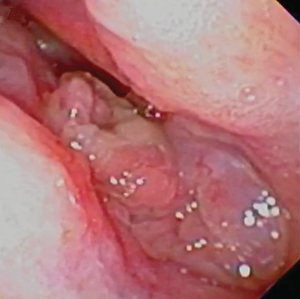

Laryngeal Mass

The larynx contains the two vocal chords, also called vocal folds,

which are flaps of tissue which vibrate in response to air passing

through the larynx, enabling the dog to make vocal sounds. The folds are

comprised of a ligament, a muscle, and a mucous membrane covering them.

In some BAOS dogs, including cavaliers but

particularly

French bulldogs, a mass of granulation tissue forms between the vocal

folds, in response to an ulceration caused by an airway malformation

condition. (See image at right.) The specific term to identify

this mass is "vocal fold granuloma", but the mass actually is not a

granuloma at all.

In a March 2025 article, in which 13 BOAS-affected dogs, including 8 French bulldogs and 1 cavalier were studied, all of the patients exhibited inspiratory effort, indicating chronic upper airway negative pressure that exposed the vocal folds to chronic irritation and trauma to the vocal folds. The irritation was attributed at least in part to gastroesophageal reflux, another common condition in BAOS breeds. In this case, surgery was deemed necessary to remove the mass from between the folds, and to reduce the negative pressure and eliminate the injury to the vocal folds caused byt eh gastroesophageal reflux. The patients in this March 2025 report also were treated with corticosteroids and antibiotics. The cavalier and 11 of the other dogs were successfully treated. The other dog had a recurrance of the mass and required a second surgerial removal.